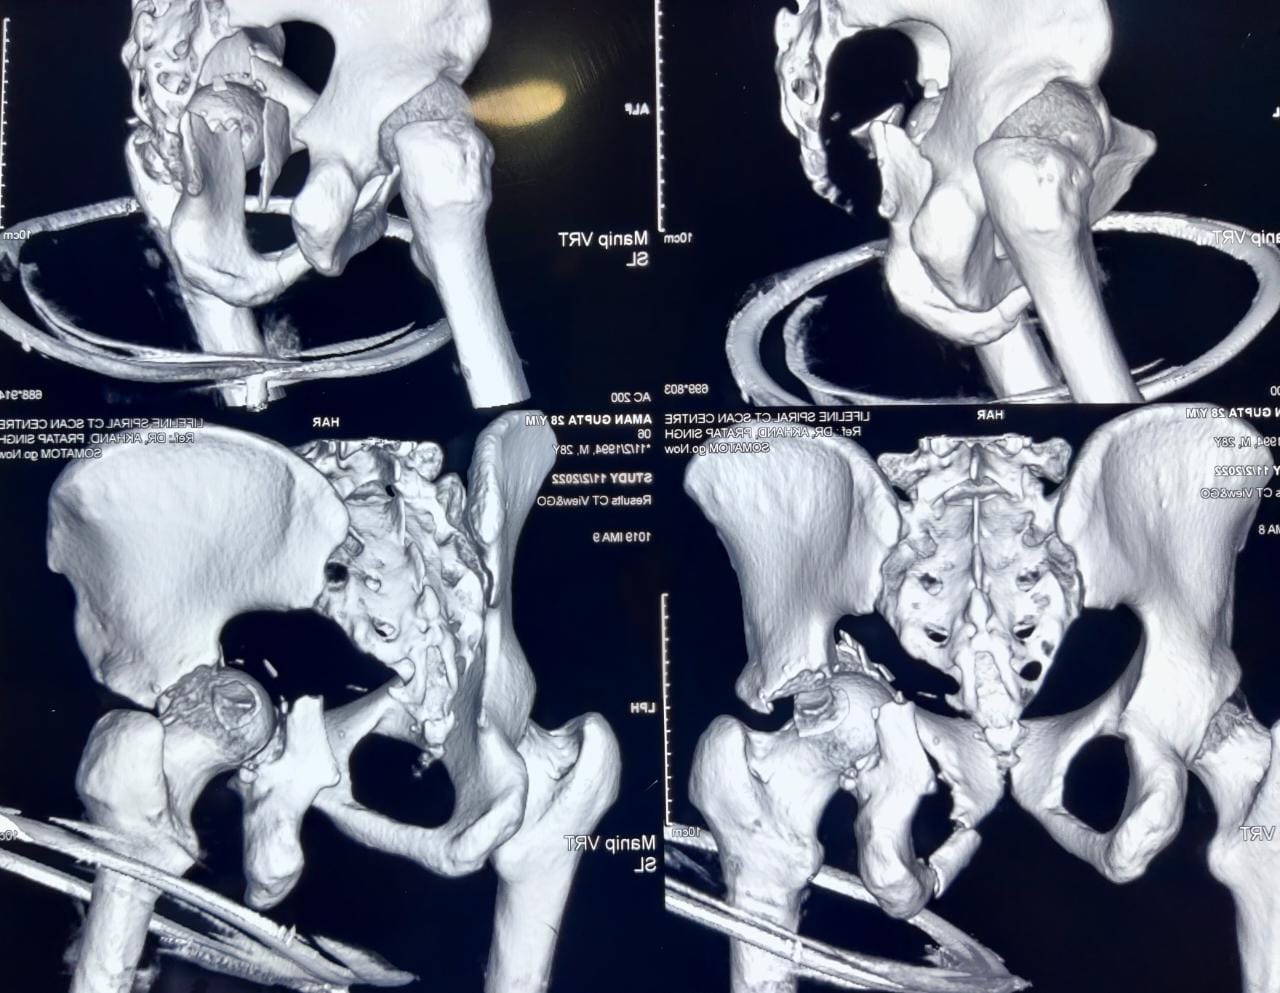

Pelvi Acetabular Trauma and Reconstruction

We as a tertiary care centre in the field of orthopaedics encounter a lot of complex trauma with extremely serious injuries around the hip

The injuries encompass hip dislocations with or without ACETABULAR fractures.

These fractures require urgent and precise surgical fixation to achieve the ultimate outcome. We at our centre routinely perform such surgeries.

Case 1